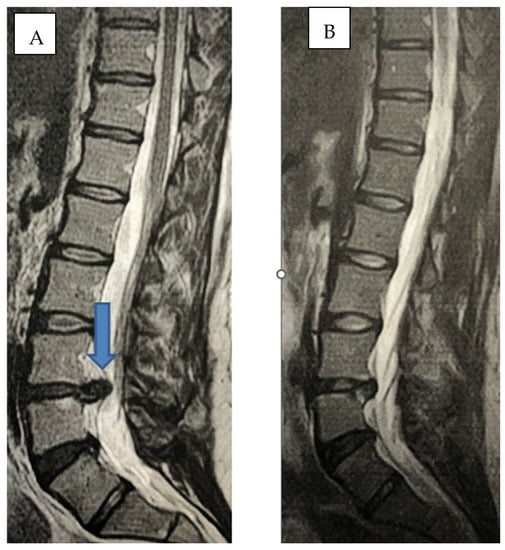

2.1. Infiltration Technique